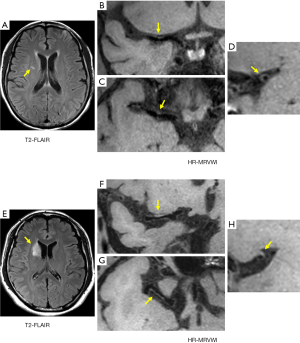

For the SSI group, no eccentric or concentric wall thickening was found in 5 of the 43 patients (11.6%). In the LSI group, all patients had eccentric or non-eccentric wall thickening of the MCA on the ipsilateral side of the cerebral infarction. A comparison of the number of quadrants with plaque formation and location of plaque distribution between the SSI group and LSI group is given in Tables 2 and 3, respectively. For the SSI group, the plaque in 13 patients involved only one quadrant, and the proportion was significantly higher than in the LSI group (34.2 vs. 7.1%, P=0.006). Figure 1 shows representative HR-MRVWI images of two patients with SSI and LSI, respectively. The plaque in both patients involved only one quadrant.

Furthermore, the 13 plaques were more frequently located in the superior (46.2%) and dorsal (38.5%) sides of the vessel wall. The occurrence of plaques involving two or more quadrants was approximately the same in the two groups, and plaques involving two quadrants were the most common distribution pattern in both groups: 17 and 19 plaques in SSI and LSI groups, respectively (Table 2). The plaque distribution in four quadrants was similar between the two groups. The ventral side was a relatively commonly involved quadrant, whereas the dorsal side was a relatively rarely involved quadrant.